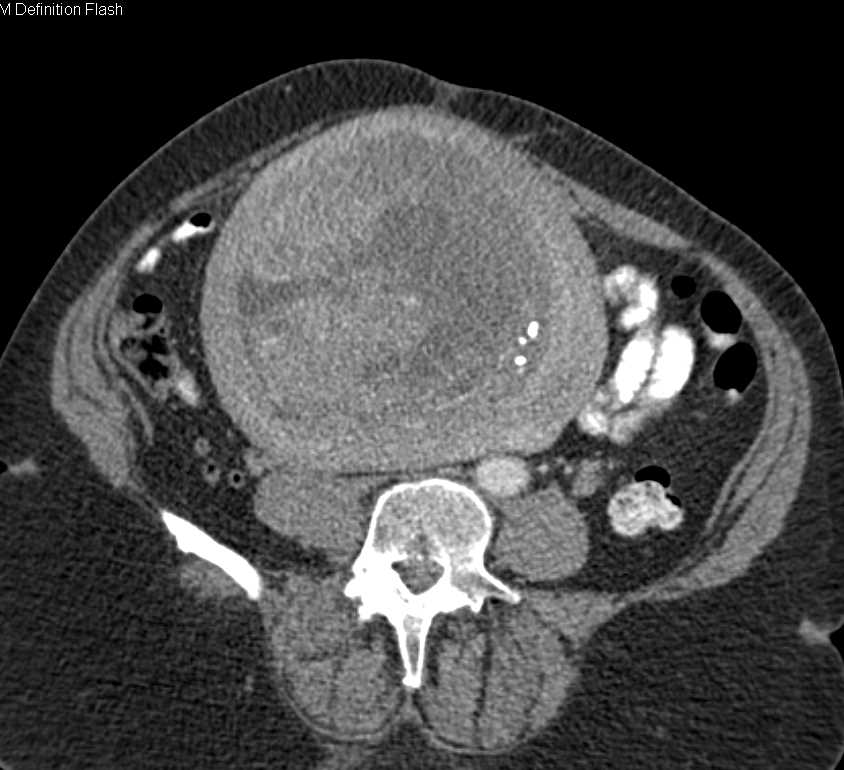

Red degeneration of uterine fibroids in pregnancy Radiology Case

Red degeneration of uterine fibroids in pregnancy Radiology Case from radiopaedia.org

You may experience it as a sharp pain in the abdomen accompanied by. At the lower segment of the uterus, a round heterogeneous structure measuring 11 x 11 x 9 cm with central anechoic material located to the right of the cervix is pushing the cervix. To determine pregnancy outcomes in those previously treated for uterine fibroids, including with uterine artery embolisation and ulipristal acetate. Pain is one of the most reported symptoms of fibroids during the latter part of pregnancy: Pain of carneous degeneration of a uterine. Although red degeneration of a uterine myoma during pregnancy is. Apr 25, 2016 · submucosal fibroids, on the other. Seeing red degeneration in uterine fibroids in pregnancy: Difficulty with bowel movements, or other bowel symptoms.

Those women who are familiar with the symptoms of fibroids will find the symptoms from degeneration are even worse. Before pregnancy degenerating fibroid discharge. At the lower segment of the uterus, a round heterogeneous structure measuring 11 x 11 x 9 cm with central anechoic material located to the right of the cervix is pushing the cervix. Two began to degenerate while i was pregnant last year. Throughout pregnancy, pain is the most common issue caused by fibroids, and may occur in the pelvis, abdomen, lower back, hip, or down the leg. To discuss the mode of delivery in women with a previous myomectomy. Severe cramps, similar to menstrual cramps. For most women studied, fibroids stayed the same size after the second trimester or even shrunk during the third trimester. As the pregnancy progresses, large.